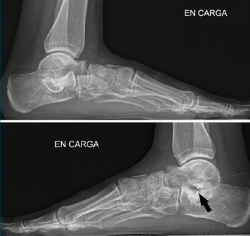

Figura 10. Tras la cirugía: primer caso a la izquierda, segundo caso a la derecha. Las flechas señalan el pie intervenido.

A los 6 meses (Figura 10), la evolución es correcta, con corrección clínica y radiológica del plano/valgo y manteniendo cierta movilidad de la articulación subtalar (15°).

En el primer caso (Figura 11), presenta el siguiente balance articular: flexión = 45°; extensión = 15°; inversión = 10°; eversión = 5°. Valgo talar de 10°. Refiere molestias discretas en el seno del tarso a la hiperextensión. Marcha correcta. Escala AOFAS del tobillo: 82 (30-42-10) . Los ángulos radiológicos finales son: Moreau-Costa-Bartani interno = 134°; declinación talar = 18,3°; Meary = 1,6°; Kite = 16,2°; taloescafoideo= 63,3°.

En el segundo caso (Figura 12), presenta un balance articular: flexión = 45°; extensión = 20°; inversión = 10°; eversión = 5°. Valgo del talón de 9°. La paciente refiere alguna molestia sin definir en el retropié y realiza una marcha correcta. Escala AOFAS del tobillo: 84 (30-44-10). Los ángulos radiológicos finales son: Moreau-Costa-Bartani interno = 131°; declinación talar = 13,8°; Meary = 1,1°; Kite = 15,1°; taloescafoideo = 77,4°.

Figura 12. Radiografía de perfil de ambos pies del segundo caso. Flecha en la endortesis del pie intervenido.